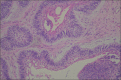

Context: Ameloblastomas are benign tumors of the jaws with locally invasive capacity.

Results: The mean age of the patients at presentation was 35.1 ± 16.8 years with a slight female preference. The peak prevalence was in the 11- to 20-year age group and declined with increasing age. Total 75 patients were black and 37 were white, for a 2:1 black: white ratio. The location of the ameloblastomas showed a marked predominance in the mandible (84.8%) and 69% of the cases presented with a multilocular radiographic appearance. The tumor was associated with an embedded tooth in 14 cases (12.7%): nine unilocular and five multilocular ameloblastomas. The maximum radiological extension of the lesions on panoramic radiographs was 0.5-20 cm (mean ± SD: 5.2 ± 3.3 cm) and most cases were symptom-free (75.9%). Solid/multicystic ameloblastoma was the most common clinicopathologic subtype. There was an association between the clinicopathologic subtypes and radiographic appearance (P < 0.001). Recurrence was observed in 13.3% of cases.